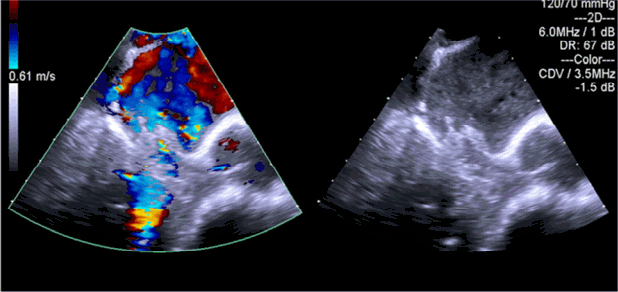

Figure 2.

Transthoracic echocardiogram shows a frail mass (white arrow) dangling from the antero-lateral leaflet of the mitral valve (1.07 ± 0.45 cm).

32세 남자가 내원 당일부터 시작된 호흡곤란 및 발열을 주소로 응급실을 방문하였다. 8년 전 고혈압 및 만성 신부전을 진단받고 2년 전 말기 신부전으로 진행되어 타 병원에서 유지 혈액투석 중이었으며, 3개월 전 유사한 증상으로 폐렴 진단 하에 항생제 치료를 받았던 병력이 있었다.내원 당시 호흡곤란 및 발열 외에 기침, 가래 등의 동반 증상은 없었으며, 활력 징후는 혈압 131/89 mmHg, 심박동수 108회/분, 호흡수 30회/분, 체온 37.8℃였다. 청진상 양측 폐 영역에서 수포음이 들렸으나 빈맥으로 인하여 심잡음은 확인되지 않았다. Osler's node나 Roth spot 등은 관찰되지 않았다. 동맥혈 가스 분석에서 pH 7.434, 이산화탄소분압 34.3 mmHg, 산소분압 66.0 mmHg, 중탄산염 22.5 mmol/L, 산소포화도 92.7%였다. 말초혈액 검사 결과는 혈색소 7.2 g/dL, 적혈구 용적률 23.7%, 백혈구 12,970/mm3 (중성구 84.9%), 혈소판 274 × 103/mm3였고, 혈청 생화학 검사 결과는 혈중요소질소 34.7 mg/dL, 크레아티닌 10.46 mg/dL, 총 단백질 6.7 g/dL, 알부민 3.6 g/dL, 나트륨 136 mEq/L, 칼륨 4.4 mEq/L, 클로라이드 98 mEq/L, C 반응성단백질(CRP) 7.80 mg/L (정상 범위: < 0.3)로 측정되었다. C3, C4, rheumatoid factor, anti-dsDNA Ab 및 anti-GBM Ab는 모두 정상 범위 또는 음성 소견이었다. 흉부 엑스선 촬영에서는 양측 폐음영이 증가되어 있는 폐부종이 관찰되었고, 이전과 비교하여 심장비대 소견이 동반되어 있었다(Fig. 1A). 흉부 전산화단층촬영에서 양측 폐부종 및 심비대, 소량의 늑막액과 심낭액이 확인되었고, 폐렴 의심 소견은 보이지 않았다(Fig. 1B).내원 초기 유지 혈액투석을 받고 있는 투석 환자에서 체액 과다에 의한 심한 급성 폐부종으로 판단하여 응급 혈액투석을 시행하였다. 투석 후 흉부 엑스선에서 폐부종은 호전되었으나 심장비대 소견은 지속되었다. 추가로 확인한 심장 표지자 검사는 troponin I 양성, troponin T 0.520 ng/mL (정상범위: < 0.099), B-type natriuretic peptide (BNP) 27,863 pg/mL (정상 범위: 5-125)로 측정되었으며, 심전도에서 심박수 102회의 동성빈맥 및 V2-3에 이상 Q파가 관찰되어 심초음파를 시행하였다. 경흉부 심초음파에서 심박출률은 64%로 정상 범위에 있었으나 양심방의 비대와 함께 승모판에 1.07 × 0.45 cm 크기의 우종 및 중증 승모판 폐쇄부전이 발견되었다(Fig. 2). 이어서 시행한 경식도 심초음파 검사 결과 승모판 전엽의 외측에 2개 이상의 다발성건삭파열(chordae rupture)과 이로 인한 중증 승모판 폐쇄부전이 확인되었다(Fig. 3).환자의 신체 검진상 immunologic phenomena인 Osler's node나 Roth spot 등은 관찰되지 않았으나, 심초음파 검사상 감염성 심내막염이 의심되어 곧바로 혈액 배양 검사를 하고, 경험적 항생제로 vancomycin을 투여하고 흉부외과로 전과하여 응급으로 개흉술을 시행하였다. 수술시 심초음파에서 보였던 1 cm 가량의 우종을 확인하고 제거하였으며 승모판치환술을 시행하였다. 내원 당일 시행했던 혈액 배양 검사 최종 결과에서 vancomycin, teicoplanin에만 감수성을 보이는 그람 양성 간균(Enterococcus faecalis)이 배양되어 vancomycin 항생제를 계속 투여하였다. 수술 후 28일째 시행한 심초음파에서 심박출률이 51%로 이전보다 약간 감소하였으나 치환된 인공 승모판이 잘 기능하고 있는 것을 확인하였고, 항생제는 총 6주 사용하였으며 와파린 용량 조절하여 술 후 51일째 퇴원하였다. 퇴원 후 외래에서 특별한 증상 없이 경과 관찰 중에 있다.